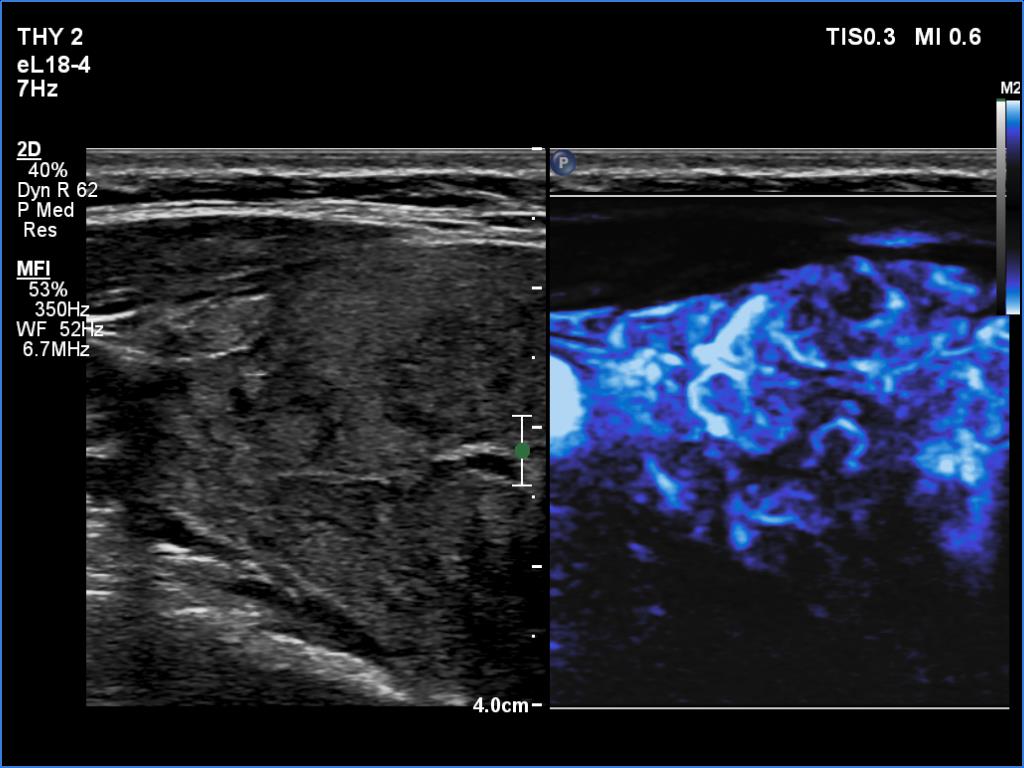

Right lobe, longitudinal scan

Right lobe, transverse scan, microflow imaging. The vascularity is increased.